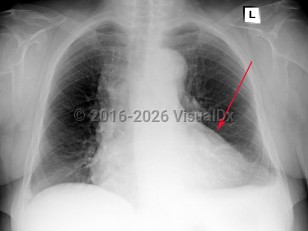

Symptoms and Signs: Acute pericarditis typically presents with sharp pleuritic chest pain, exacerbated by the supine position and improved with leaning forward. Fever and myalgias may be present but are not required features. On examination, a scratch-like friction rub (pericardial rub) may be heard, although this is present in less than 33% of cases. To make the diagnosis of pericarditis, the patient must have 2 of 4 criteria: pericardial rub, chest pain, ECG changes, and/or presence of a pericardial effusion. Chest pain has the highest incidence and is seen in 85%-90% of cases.

While not usually life-threatening, acute pericarditis can progress to cardiac tamponade or constrictive pericarditis in some complicated cases. Consider constrictive pericarditis in cases of unexplained heart failure. Tricuspid regurgitation is common in these patients and is associated with increased mortality. Other findings in constrictive pericarditis can include Kussmaul sign (a paradoxical increase in jugular venous pressure on inspiration), jugular venous distention, peripheral edema, hepatomegaly, and pericardial knock.